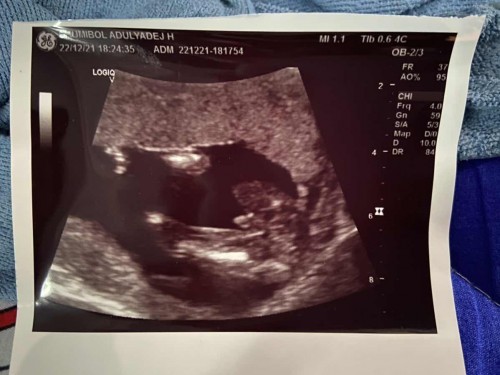

แม่บ้านไหนรู้เพศน้องแล้วบ้างคะ บ้านนี้อัลตราซาวด์มาไม่แน่ใจค่า แบบนี้ได้หญิงหรือชาย